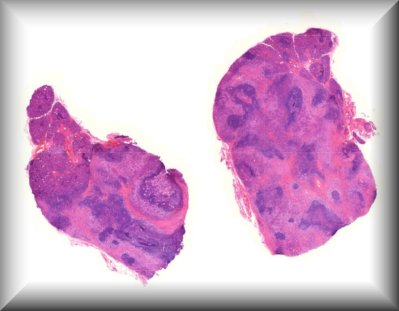

Hind M. Alkatan (Guest): A 10-month-old boy presented with a painless scrotal mass.External examination demonstrated left scrotal non-tender hard mass measuring 4x3 cm in size, with negative transillumination test. Ultrasonography of left scrotum showed a well-circumscribed, oval shaped mass with mixed echogenicity, The mass contained both cystic and solid component, with no clear visualization of the left testicle.The patient underwent left scrotal exploration with high inguinal orchidectomy |